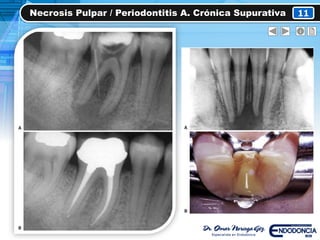

• NECROSIS PULPAR

• Total

• Evolución de la necrosis pulpar y PAC no tratadas

• Respuesta NEGATIVA a estímulos

• Sintomatología a la percusión y palpación

• RX  Zona radiolucida apical

Se produce dolor como consecuencia del gran aumento

de presión hidrostática de los tejidos pulpar y

periapicales

PX sintomático o asintomático

Necrosis Pulpar / Periodontitis A. Crónica Supurativa 11

CLÍNICAMENTE RADIOGRÁFICAMENTE

• Caries grado 3

• Pigmentación coronal

(Gris-Café)

• Fistula dental

• Exudado a través de la

fistula o el conducto

radicular

• Inflamación gingival

• Movilidad grado 1-2

• Zona radiolucida (Apical)

• Ensanchamiento del ELP

• Es posible realizar

fistulografía

PRUEBAS DE SENSIBILIDAD ANAMNESIS

• (-) Pruebas térmicas

• (+) Percusión Vertical

• (+) Percusión H.

• (+) Palpación

• Dolor a la masticación

• Sintomático o

asintomático

• Refiere sintomatología,

que no sede

completamente con

analgésicos comunes

(No pudo dormir)

TRATAMIENTOS

• Tratamiento endodóntico

• Extracción dental

1 semana

1 año